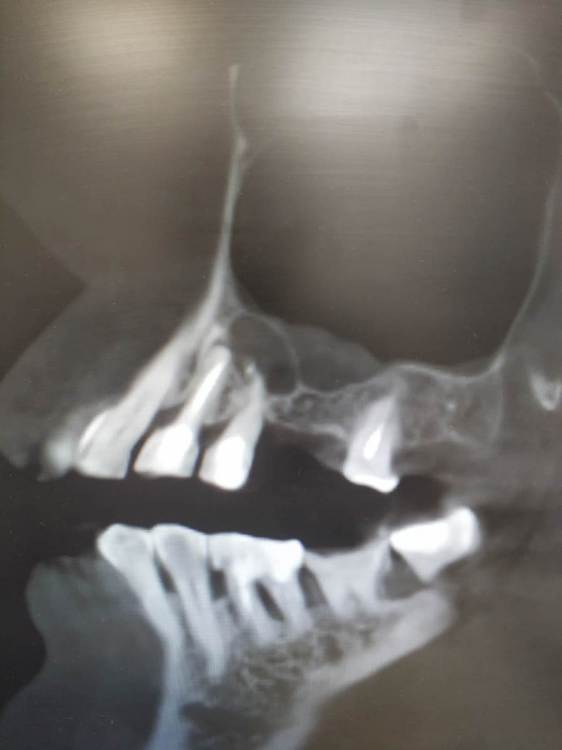

TIGER Опубликовано 29 июля, 2023 Поделиться Опубликовано 29 июля, 2023 (изменено) MAH02590.MP4 Всем привет!Последние лет 5 с внедрением микроскопа в практику стало больше зубо-сохранения,меньше болтов соответственно,что меня радует)Пациент направлен коллегой ввиду невозможности ортоградной ревизии.Проведена зубосохраняющая операция,зуб сохранён.симптомов нет)видео ретро препа тут https://youtu.be/3ukPvjdicW8 MAH02590.MP4 Изменено 29 июля, 2023 пользователем TIGER 3 1 Ссылка на комментарий

Raystom Опубликовано 29 июля, 2023 Поделиться Опубликовано 29 июля, 2023 (изменено) @Fin не автор, но подвижности не наблюдал. Вот пример. Подвижности нет. Изменено 29 июля, 2023 пользователем Raystom 1 2 Ссылка на комментарий

TIGER Опубликовано 29 июля, 2023 Автор Поделиться Опубликовано 29 июля, 2023 @Fin спасибо!Канал пломбирую IRM,гемостаз применение артикаина 1:100,капрамин,кости там норм,подвижности нет,плюс сохранения зуба,что организм нам союзник,в отличие от импланта) 1 Ссылка на комментарий